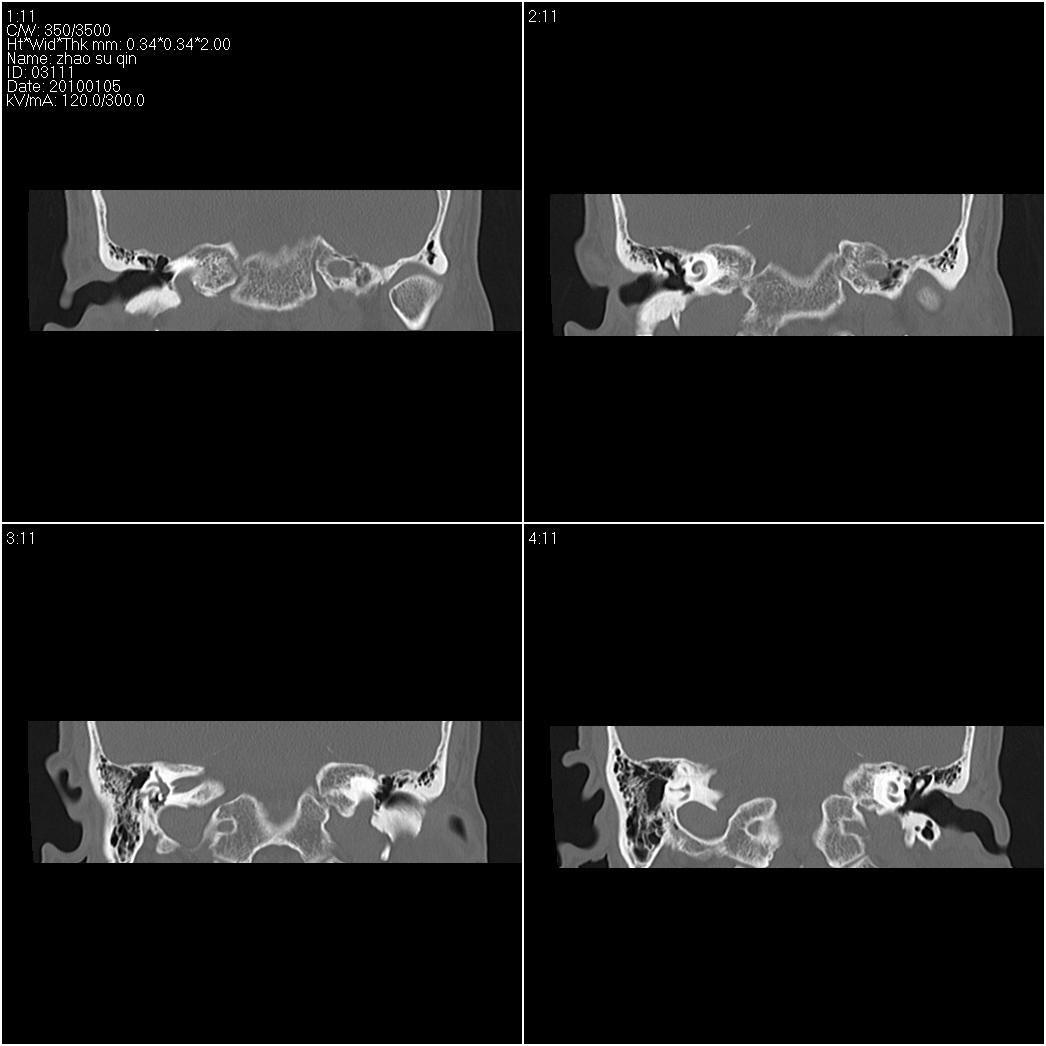

标题: CT24015:一个头部外伤患者进行鉴定,除了左侧筛板骨折,哪 [打印本页]

标题: CT24015:一个头部外伤患者进行鉴定,除了左侧筛板骨折,哪

左眶下裂部好像有骨折 似有小碎骨片

1)左侧筛板骨折。2)双侧筛窦炎症(或积血)。